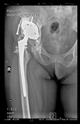

The direction of the cup stem was determined by the guide wire. The aiming device was needed to introduce this wire. After removing the aiming device, the next step was the drilling. Since a cannulated drill bit was used, the previously installed wire could guide the process. A self-positioning reaming tool was then used in the drilled channel. In the prepared cavity, the cup was fitted perfectly. Of the two stemmed cups available to us, the McMinn cup (Waldemar Link, Hamburg, Germany) had the simpler geometry and was therefore chosen. The stemmed cup was inserted according to the manufacturer’s recommendation. In the presence of a significant bone defect, a synthetic bone graft may be impacted for substitution.

The radiological examination allowed us to verify the close bone-to-implant contact and the unchanged position of the implant during follow-up.

In all the cases operated with the above-described targeting procedure, the stems of the cups remained between the cortical bone surfaces without perforation of the linea terminalis, as shown by postoperative radiographs. There were no complicated surgical situations. In 16 cases, the wound healings were uneventful, and the hips were able to bear weight again after postoperative rehabilitation.